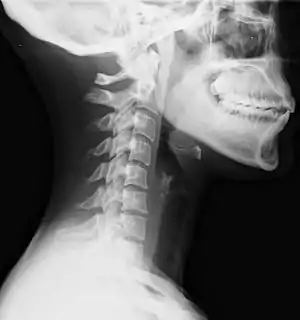

| Lateral view X-ray of whiplash showing a loss of normal lordosis of the cervical spine | |